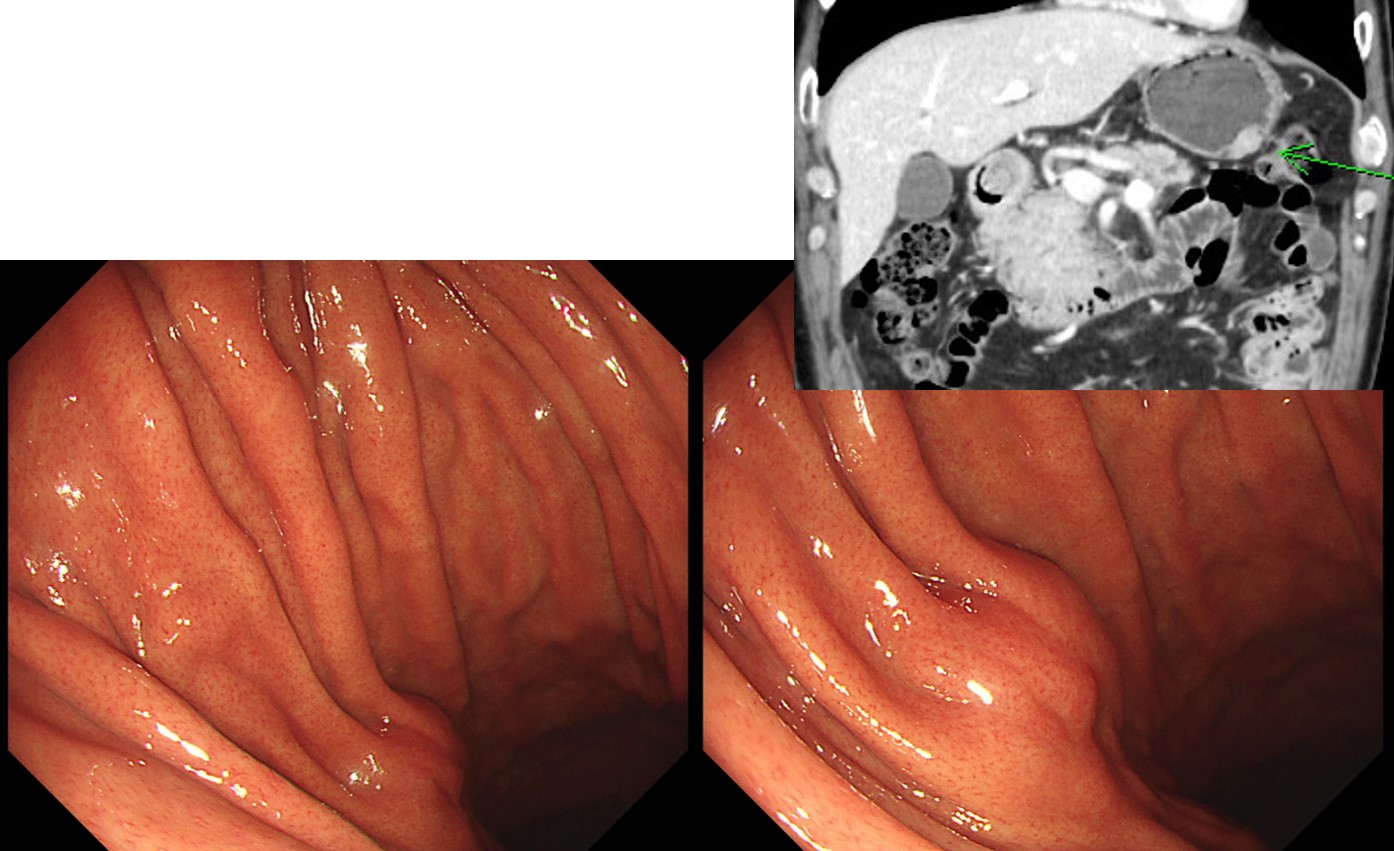

À§¿°È÷ ¹ß°ßµÈ ÀÛÀº gastric SMT´Â ´ëºÎºÐÀº Ä¿ÁöÁö ¾ÊÁö¸¸ ¹æ½ÉÀº ±Ý¹°ÀÔ´Ï´Ù. ºÐ¸í Ä¿Áö´Â °æ¿ìµµ Àֱ⠶§¹®ÀÔ´Ï´Ù. ¾Æ·¡ Áõ·Ê´Â ´ëÀå¾Ï ȯÀÚ¿¡¼­ ¿ì¿¬È÷ ¹ß°ßµÈ À§ SMT¿´½À´Ï´Ù. ÃßÀû°üÂûÀ» ±ÇÇÏ¿´À¸³ª follow up loss µÇ¾ú½À´Ï´Ù. 6³â¸¸¿¡ ¿À¼Ì´Âµ¥ Á¦¹ý Ä¿Áø »óÅ¿´½À´Ï´Ù. CT °Ë»ç ÈÄ ¼ö¼úÀ» ÇÏ¿´½À´Ï´Ù.

(2012. F/61)

Stomach, wedge resection: Gastrointestinal stromal tumor of high risk of malignant potential by proposed modification for adjuvant therapy (2008) (see note);

1) tumor size: 6.5x4 cm

2) mitosis: 6/50 HPF (high powered fields)

3) histological type: mixed spindle and epithelioid

4) necrosis: absent

5) cellularity: intermediate

6) cellular atypia: moderate

7) invasion into mucosa: absent

8) resection margin involvement: absent

Note: High risk by NIH (2002) and High risk (55%) of progressive disease by Miettinen (2006).

. DOG-1 : Positive in tumor cells

. Ki-67 : Positive in about 10% of tumor cells

. C-KIT (CD 117) : Positive in tumor cells